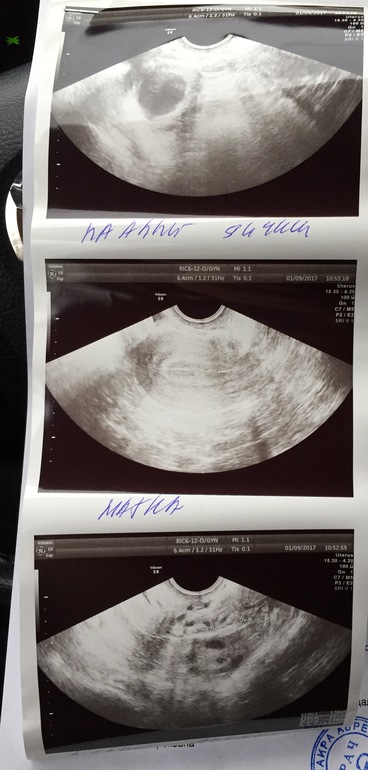

УЗИ после положительного теста на О. клеар блю

С утра сделала УЗИ. Ниже результаты. По О. специалисте сказалась что есть косвенные признаки, что О. была. Но в првом яичнике есть доминантный фолликул. 13 иду на повторное УЗИ, посмотреть была ли О., так как мне летом ставили СПКЯ,хотя сейчас врач сказала, что все нормально. Может кто разбирается в УЗИ?Она мне толком ничего и не объяснила.

Овуляция уже была - эндометрий соответствует второй фазе цикла и как подтверждение обули - наличие свободной жидкости, узистка, простите, должна это знать, не зачем идти на повторное УЗИ, а в правом яичнике - подвергнется ретроградному развитию, должен)

У вас все хорошо. Овуляция еще не наступила. Есть доминантный фоликул в пя

Он еще не лопнул. Когда лопнет должна выйти яйцеклетка из яичника и тогда возможно зачатие

Вот врач мне и сказала,что либо лопнет,либо киста и нужно сделать УЗИ 13.01.17

О уже была т.к есть свободная жидкость. Эндометрий хороший. Не переживайте.

я тоже считаю что О еще не было, т.к ЖТ нет,вот будет на днях, а жидкость в неб количествах это вариант нормы /физиологическая норма.У меня тоже до О была жидкость в неб кол-ве, потом ДФ лопнул и была и жидкость и ЖТ. ДФ в среднем на 2 мм в день растет.. так что ждите О)))